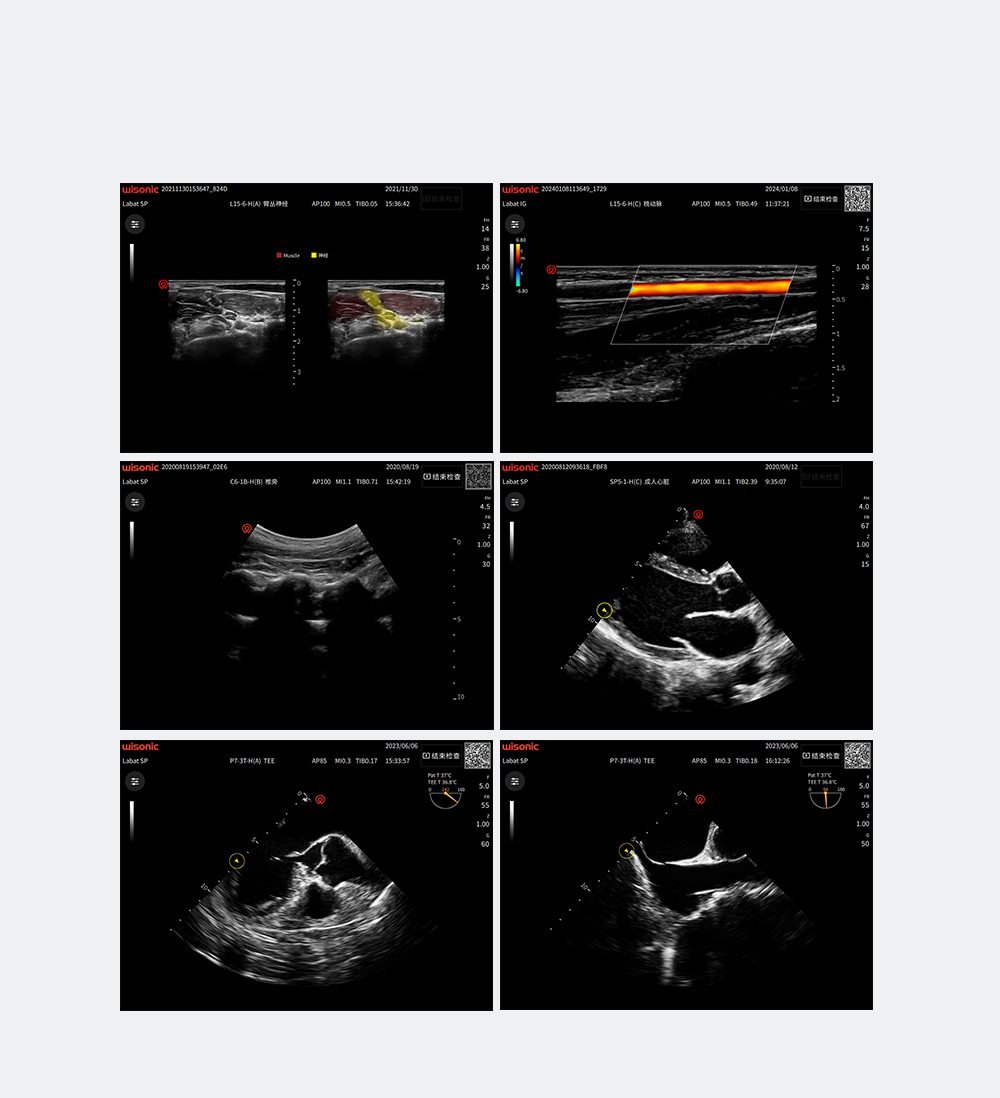

Excellent Clinical Images

Application pictures

Product pictures